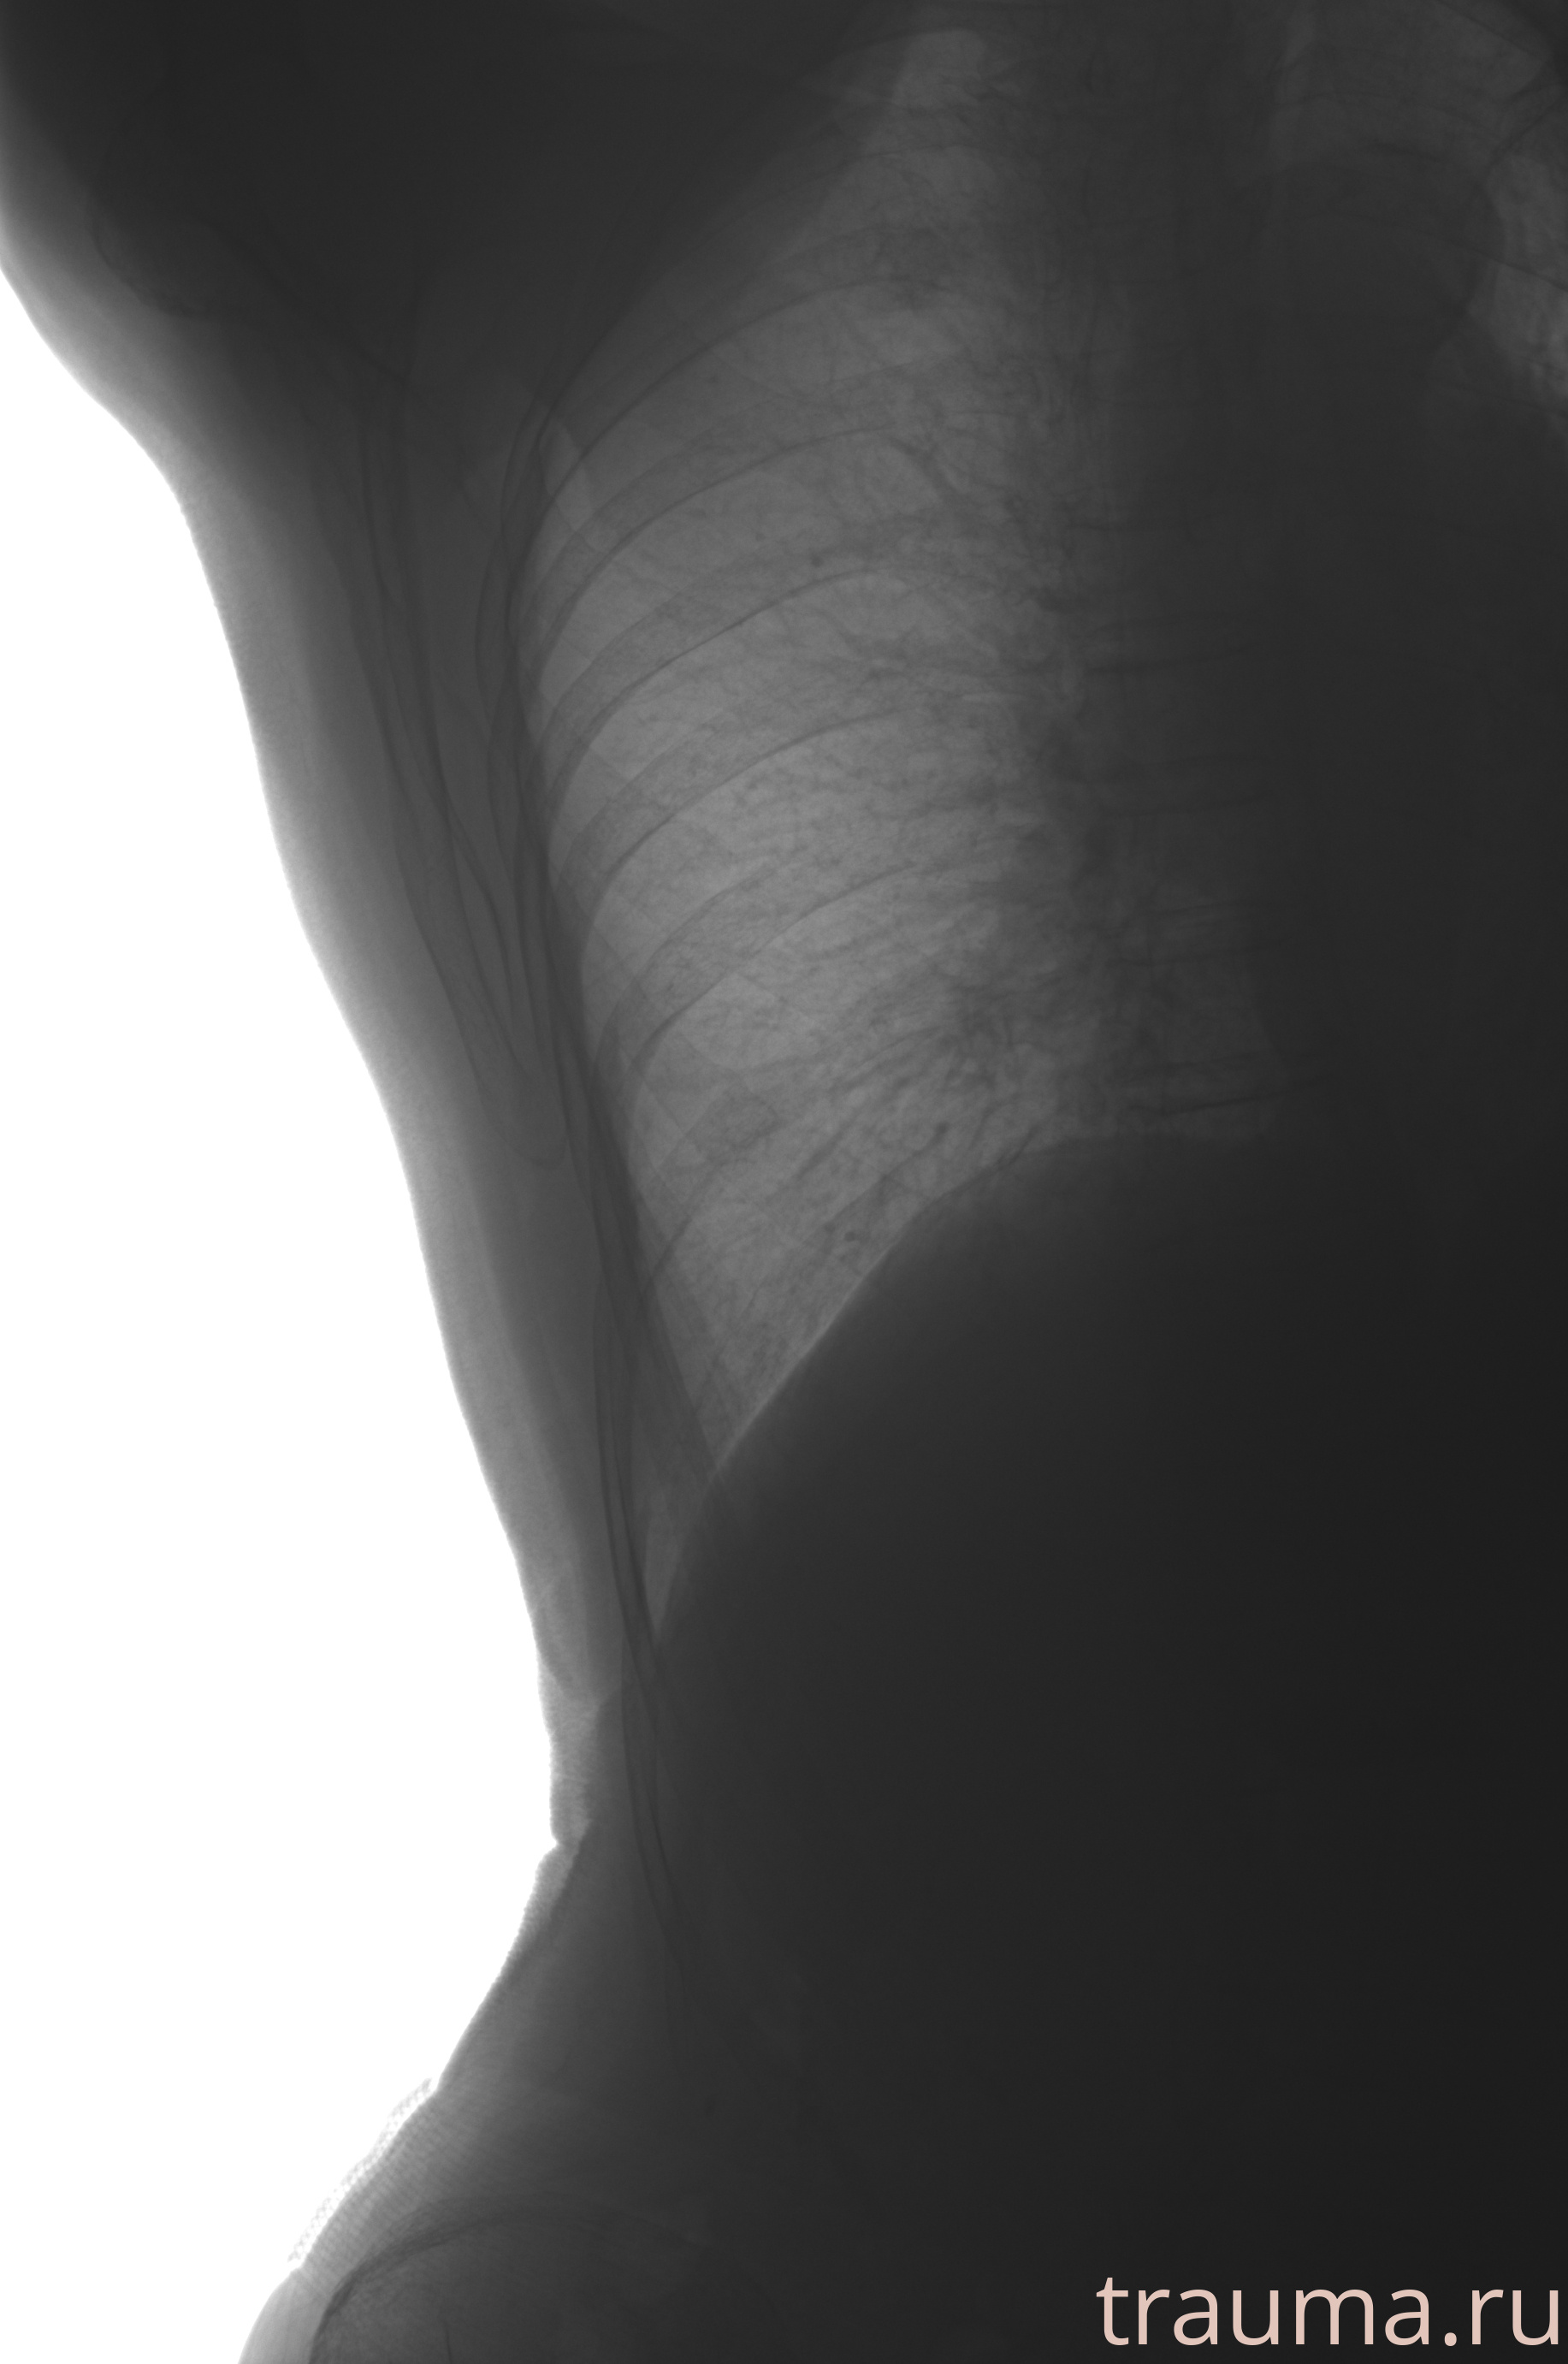

Рентгенограммы

Рентген на дому: по вашему адресу приезжает врач-рентгенолог, травматолог-ортопед с мобильным рентгеновским аппаратом, проводит диагностику травмы или заболевания, делает необходимые рентгенограммы, дает рекомендации по дальнейшему лечению. Получить качественные снимки в домашних условиях возможно благодаря уникальной методике, разработанной МосРентген Центром для института  Склифосовского

при переломе шейки бедра и пневмонии от компании МосРентген Центр - партнера Института имени Склифосовского